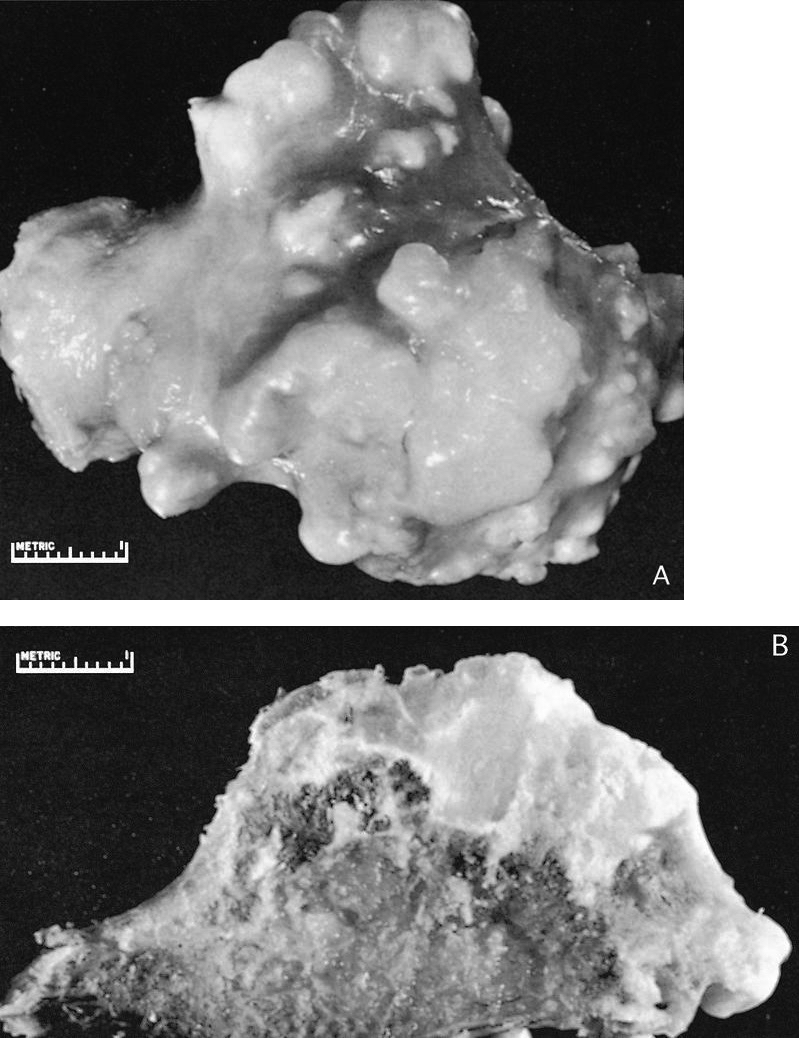

Gross description

- Pedunculated or sessile bony lesion with hyaline cartilage cap

Gross images